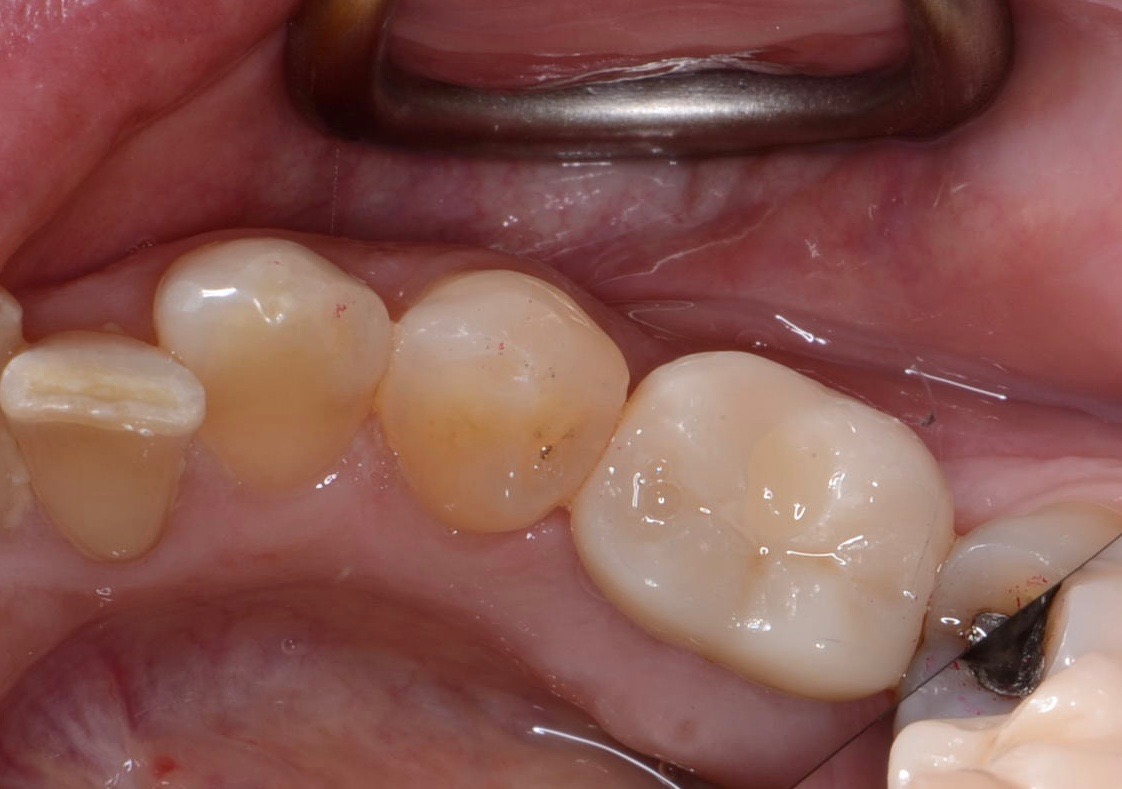

Fig 14. Clear resin cement left on the implant abutment.

Figure 14

Fig 15. Implant abutment following cement removal.

Figure 15